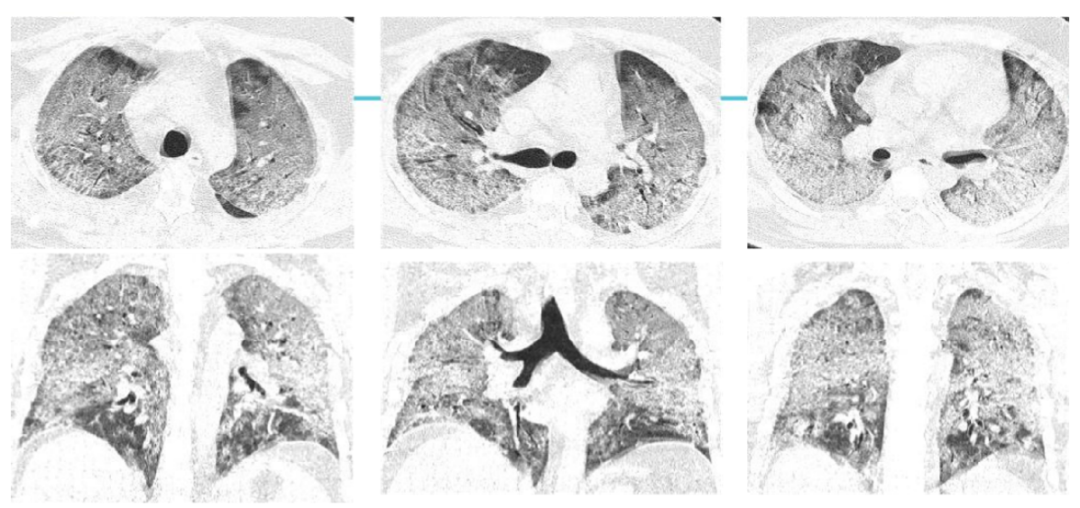

案例三,30歲,男性,確診病例

胸片顯示雙肺彌漫性病變

影像所見:發(fā)熱12天,胸悶、氣喘7天。胸部CT顯示兩肺彌散性磨玻璃影,呈“白肺”改變,其內(nèi)可見空氣支氣管征、雙側(cè)膈面上抬。

從這3個(gè)確診新冠肺炎呈“白肺”病例來看,“白肺”多見于老人、兒童以及帶有基礎(chǔ)病的新冠患者,病灶可發(fā)生在肺內(nèi)任何肺葉,病灶形態(tài)特點(diǎn)也是多樣化,符合病毒性肺炎的影像表現(xiàn)。從影像學(xué)角度出發(fā)重點(diǎn)在于快速評估病情,提升人工讀片的客觀性。 “啄醫(yī)生閱片機(jī)器人??新冠肺炎CT影像輔助分診與評估系統(tǒng)”可以準(zhǔn)確地識別新冠肺炎的典型影像表現(xiàn)如雙肺外周胸膜下多發(fā)的磨玻璃影、小葉間隔增厚或合并鋪路石征等,對于部分患者由于影像表現(xiàn)早于臨床癥狀,更具有早期發(fā)現(xiàn)、早期診斷的優(yōu)勢。